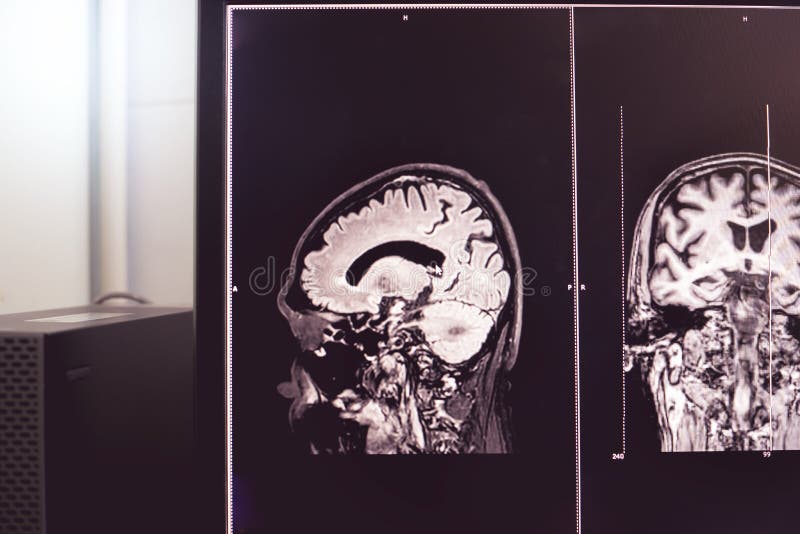

MRI Brain Dementia Stock Image. Image Of Science, Medicines - 105443423

www.dreamstime.com

www.dreamstime.com

mri gehirn demenz dementia

Brain MRI And Dementia Stock Image. Image Of Brain, Sagittal - 105374245

www.dreamstime.com

www.dreamstime.com

mri dementia failure dieting predict loss miethke hydrocephalus sagittal behandlung